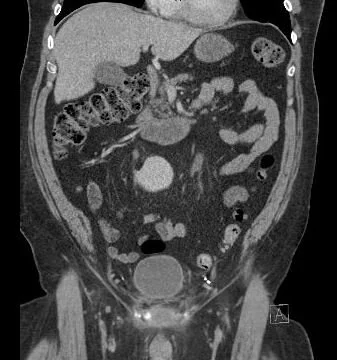

there is inflammation near the symphysis

and there is widening of the symphysis

Our patient ha a urethral leak near the pubic symphysis caused by erosion of the sphincter of the AUS.  The subsequent abscess was drained by IR and grew Klebsiella with Strep mitis and Strep bovis.  Six weeks of ceftriaxone was recommented with a PICC line. He was discharged with a Foley in place. The patient will return after the antibiotics are complete to discuss urinary diversion.